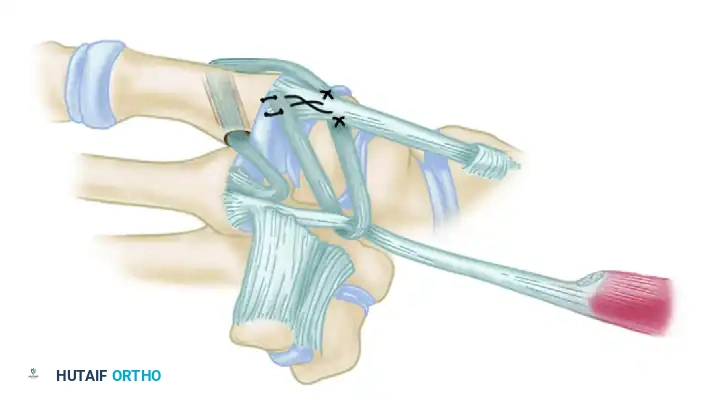

- Dorsal Anchoring: Suture the taut tendon to the dorsal periosteum of the metacarpal.

- Capsular Reinforcement: Route the remainder of the tendon proximally across the dorsal basal joint capsule, passing it beneath the EPB and APL insertions. Suture the strip under tension to the APL bony insertion.

- Final Weave: Pass the remaining tail beneath or through a short split in the intact FCR tendon just proximal to the trapezium. Route it back across the radial margin of the joint to insert into the metacarpal periosteum. Suture the tendon securely at every point where its direction changes.

Figure: Schema of volar and radial ligament reconstruction. The complex course of the tendon strip creates robust reinforcement in the volar, dorsal, and radial aspects of the joint.

Intraoperative view of the final tendon weave and capsular reinforcement.

- Intermetacarpal Securing: Pass the FCR tendon between the thumb and index metacarpal bases and secure it to itself with the same nonabsorbable suture.

*Figure C: FCR tendon passed between